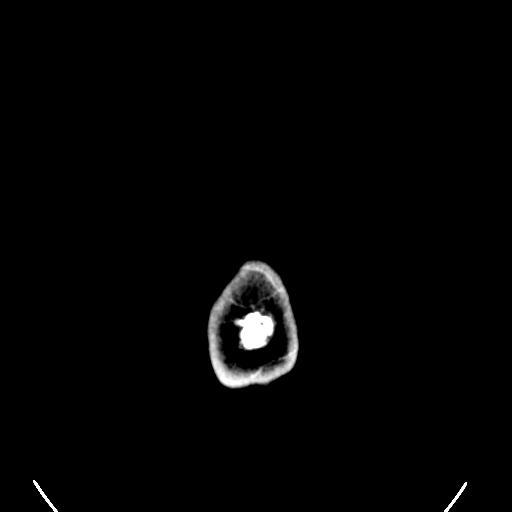

| View Original: | Computed tomography of human brain (34).png (512x512) | |||

| Keywords: Computed tomography of human brain (34).png 34 computer tomography images Check categories 2009 November 3 en wikipedia X-ray_computed_tomography 2 Computed tomography images of Mikael Häggström's brain | ||||